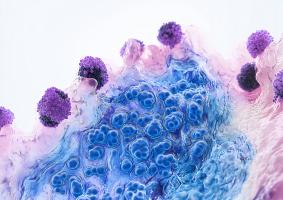

POLLUTION : Les particules fines font le lit de la maladie auto-immune

POLLUTION et DÉMENCE : Les particules fines font des corps de Lewy

Actualité publiée le 13/03/2025POLLUTION : Les particules fines expliquent 30 % du fardeau de l’asthme

Actualité publiée le 14/08/2024POLLUTION et PARKINSON : Les particules fines attaquent aussi les neurones

Actualité publiée le 11/07/2020POLLUTION : Ses particules fines mènent à l’Alzheimer